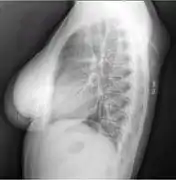

الأشعة السينية للورم الشحمي

الأشعة السينية تظهر الورم الشحمي